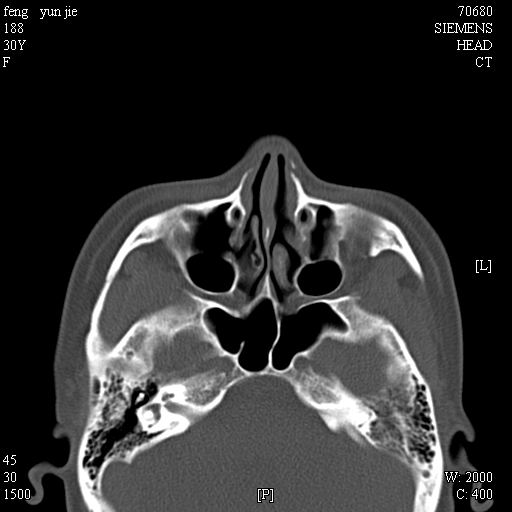

女,37岁,多年前鼻骨骨折过,现在穿刺有炎性分泌物

1)左侧鼻骨骨折(陈旧性)。2)双侧额窦及双侧筛窦炎症,伴右侧额筛窦黏液囊肿突入右侧眼眶。

额窦粘液囊肿(右侧水平额窦突入眶内上方)可能性大

考虑额窦粘液囊肿可能性大。